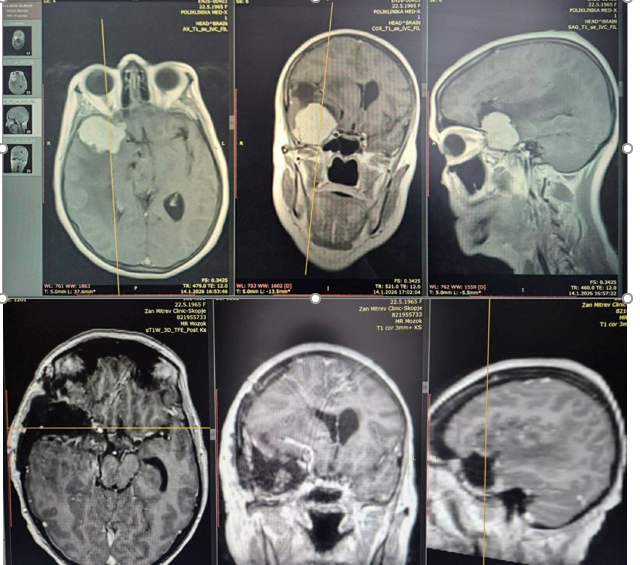

Успешно оперирана 60-годишна пациентка со комплексен тумор на базата на черепот

Пациентката беше примена со прогресивна психомоторна забавеност, проблеми со меморијата и памтењето во изминатите четири месеци, а во неколку наврати и проблем со рамнотежата и пад.

По направените радиолошки иследувања со нуклеарна магнетна резонанца, кај пациентката беше дијагностициран туморски процес во мозокот, по што следуваше индикација за оперативно лекување.

Неврохируршкиот тим во состав: проф. д-р Владимир Рендевски и д-р Михаил Таушанов, применувајќи микроневрохируршка техника, извршија успешно отстранување на овој комплексен тумор на мозокот, кој беше прилепен за базата на черепот, а во непосредна близина на витални мозочни крвни садови.

Пациентката успешно закрепнува.